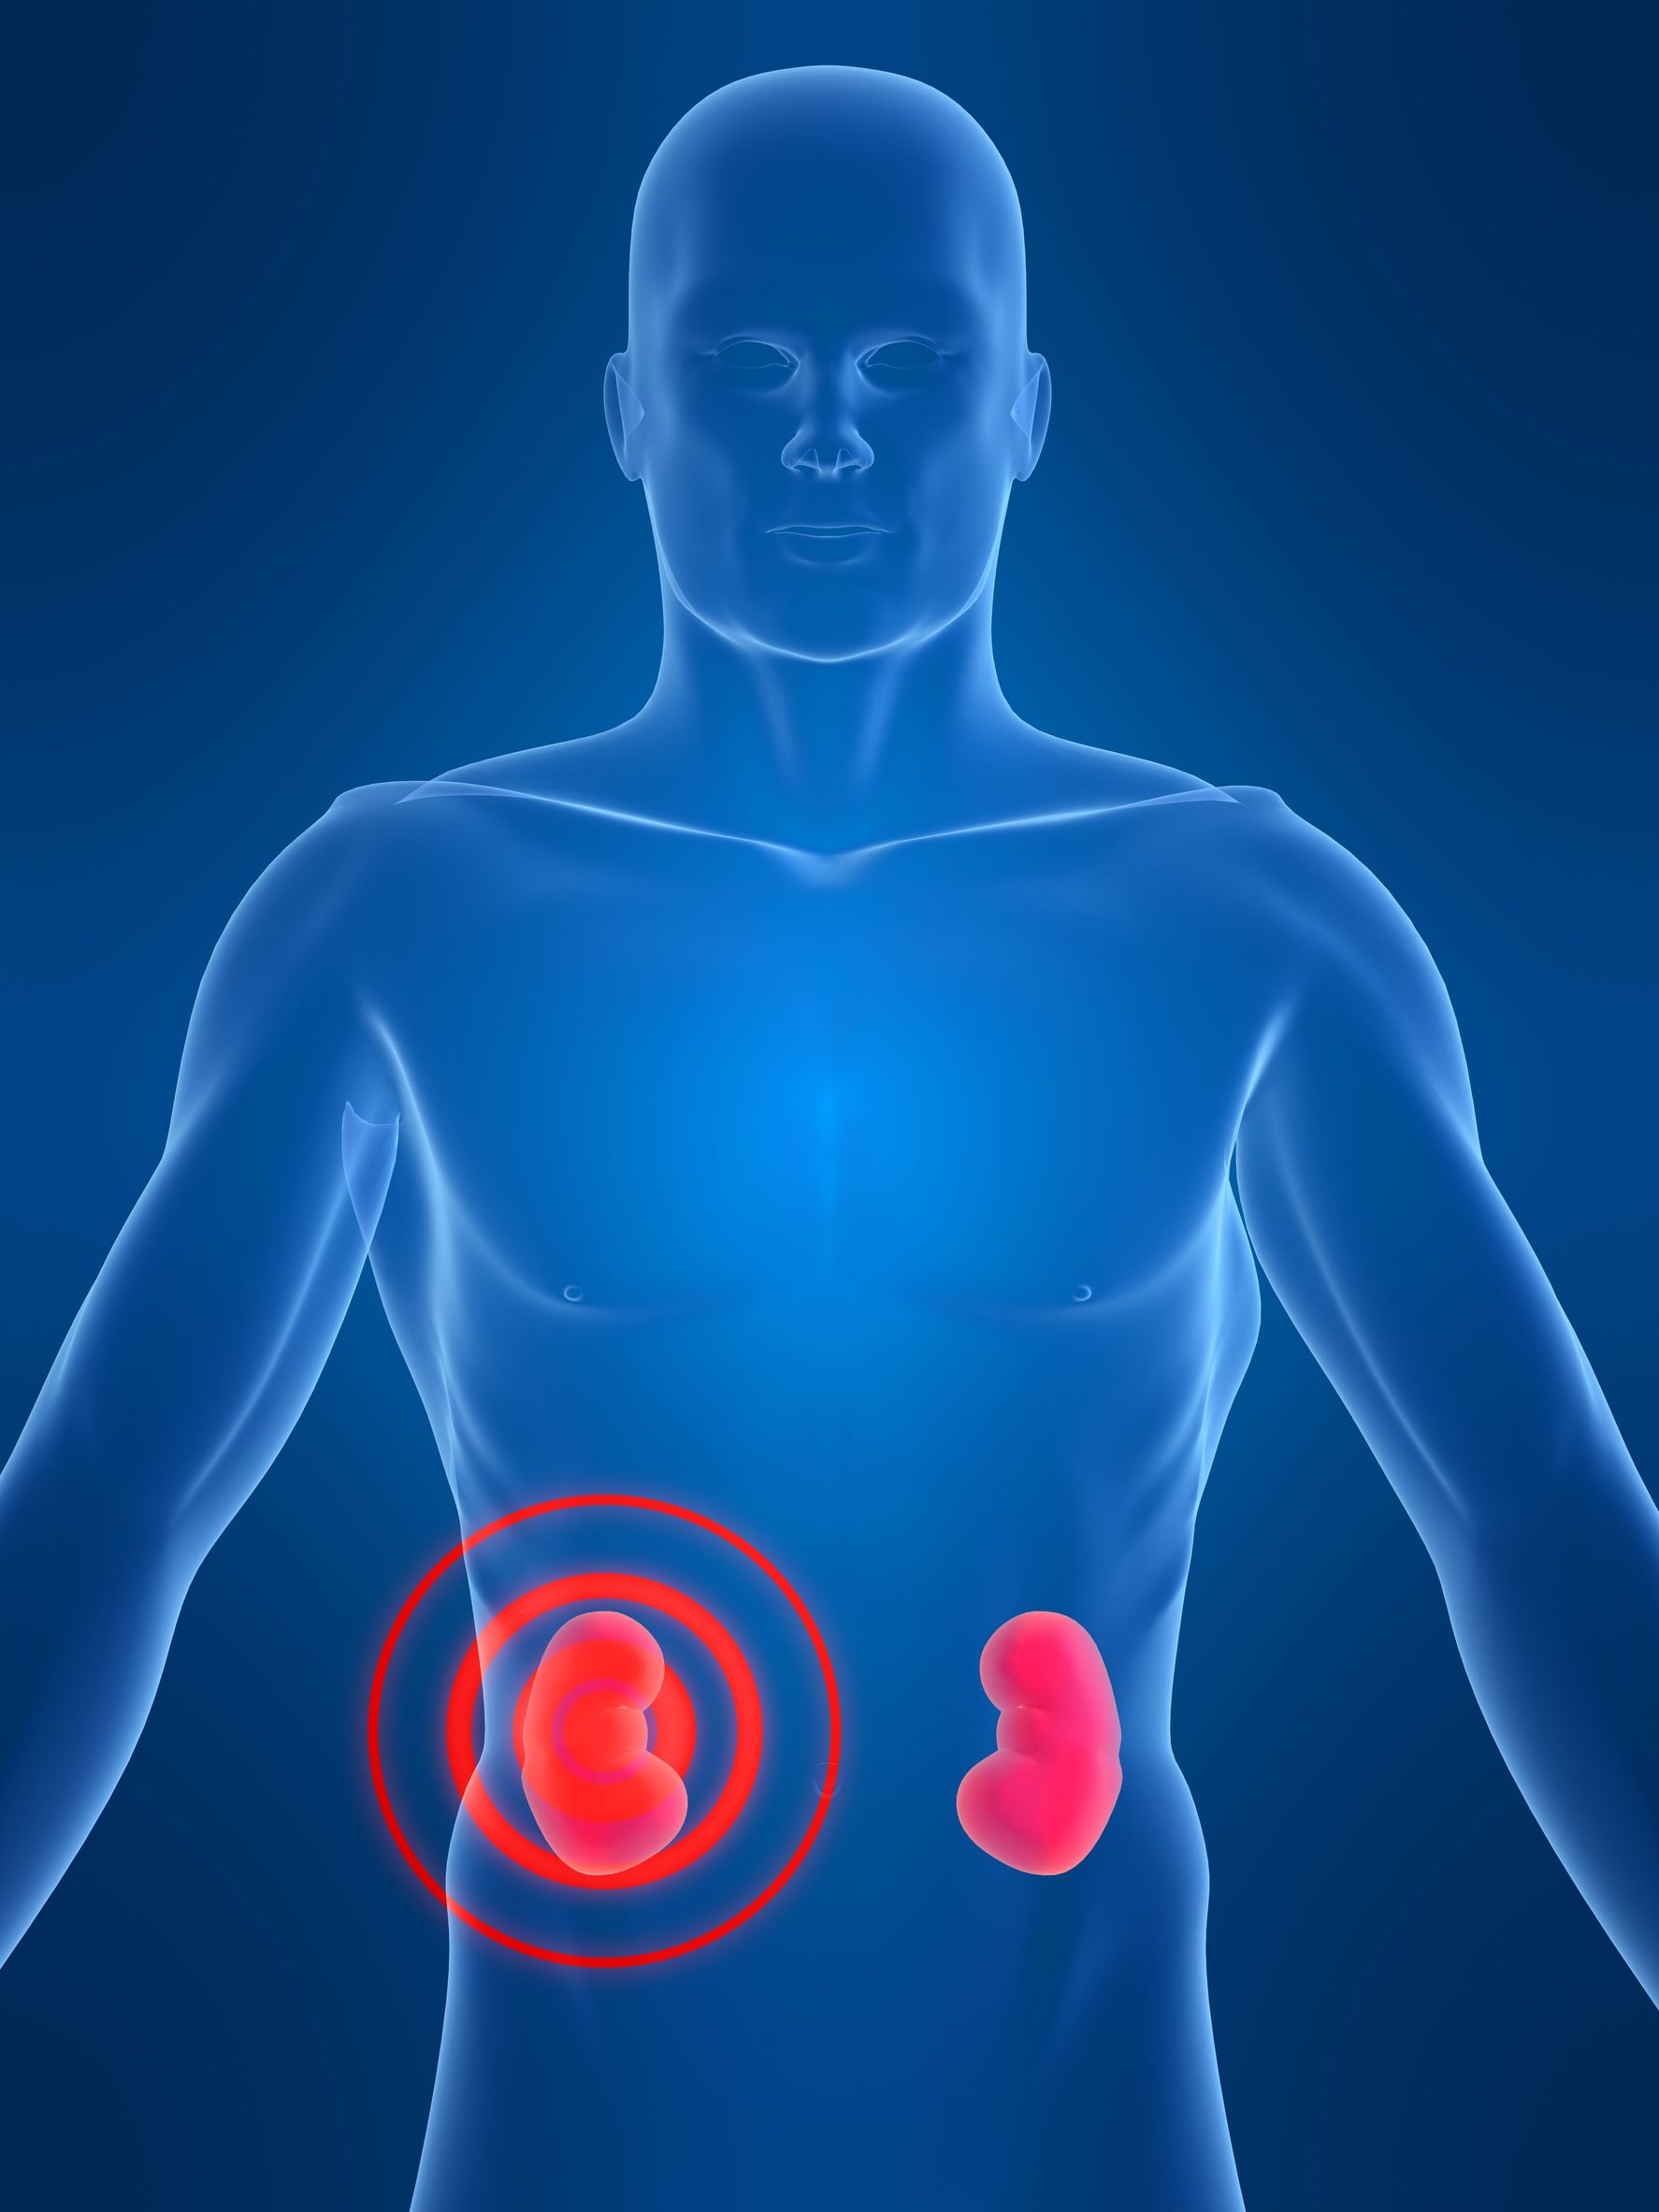

Строение почек человека: Фото и описание